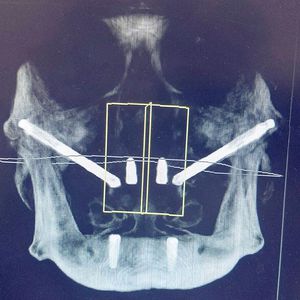

Those cheekbones tho.. ππβ’When teeth are missing for an excessively long time, the jaws resorb away, leaving inadequate bone structure to place dental implants These extra long zygomatic implants engage the cheekbones avoiding additional bone grafting procedures to the maxillofacial complex π¨ββοΈπ